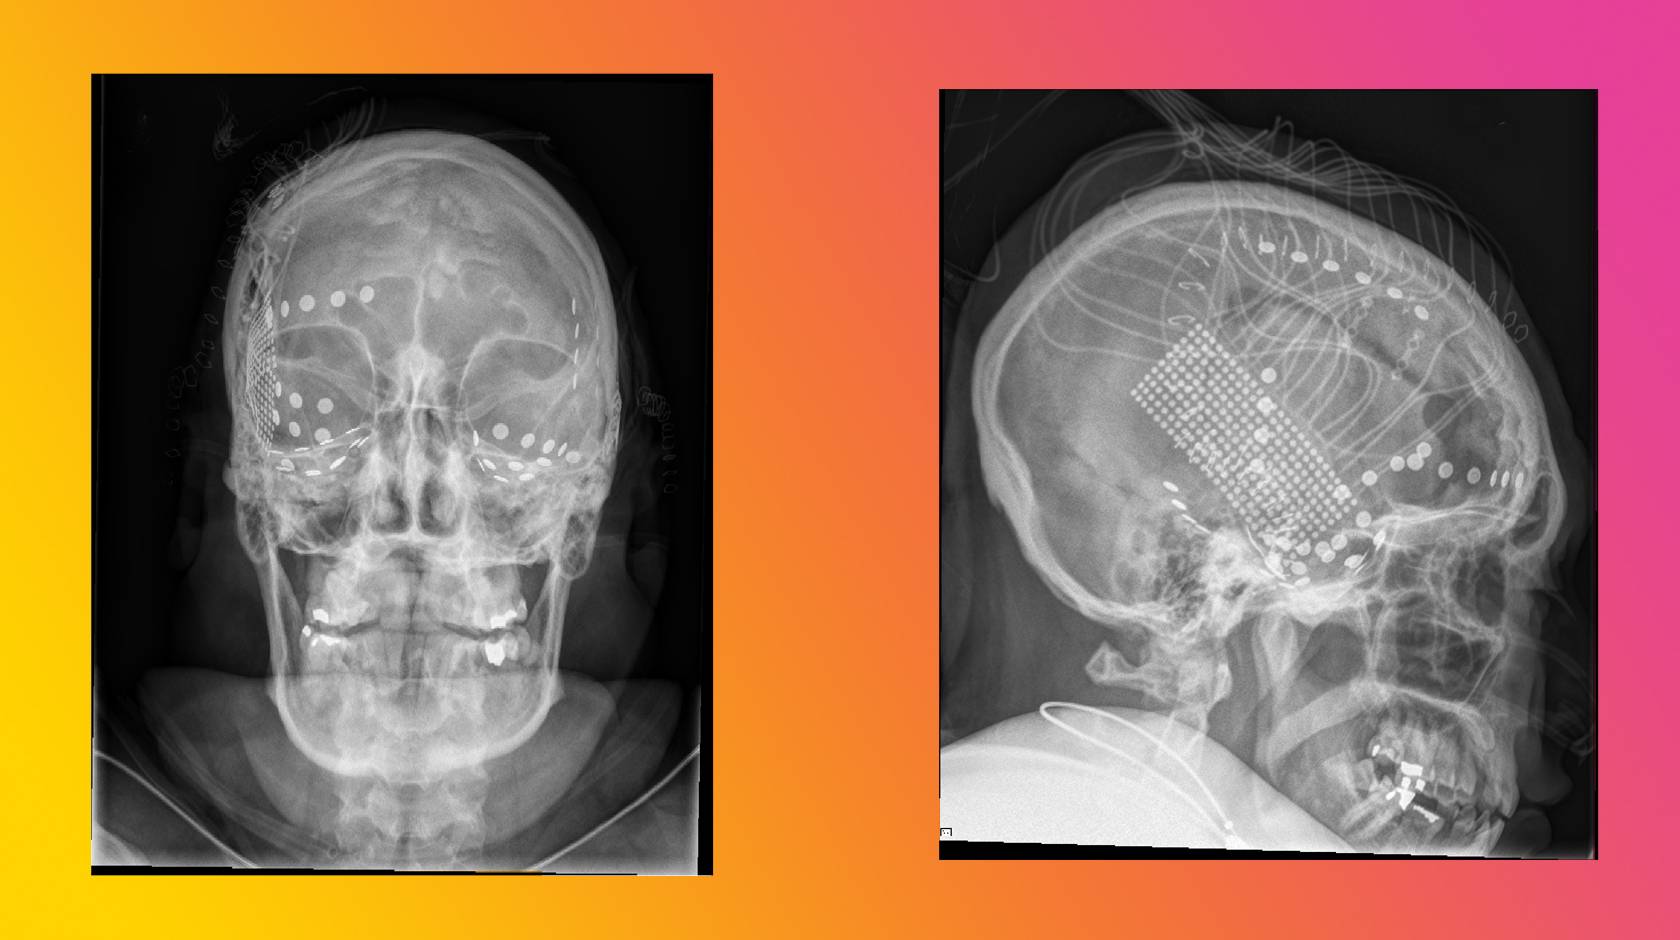

2 x-ray images of a human head showing electrodes attached to a brain

Credit: UC Berkeley

Sound familiar? You might think this clip is a recording of someone playing a spaced-out interpretation of Pink Floyd’s “Another Brick in the Wall, Part 1” on a keyboard with the synth turned up to 11. But the truth is stranger still: it’s actually a reconstruction of the song derived from brain waves of a person listening to a recording of the original.

The person whose thoughts you just heard was a patient being prepared for epilepsy surgery, which entails opening the skull to access the surface of the brain. This brave patient agreed to let researchers blast dad rock in the OR, and also to attach electrodes to their brain, which “recorded” the electrical activity in the brain’s speech and language processing centers.

The reconstructed tune shows the feasibility of recording and translating brain waves to capture the musical elements of speech, as well as the syllables. These musical elements — rhythm, stress, accent and intonation — carry meaning that the words alone do not convey. For people who have trouble speaking, such recordings could help reproduce the musicality of speech that's missing from today's robot-like reconstructions. The research was funded by the National Institutes of Health and the public-private BRAIN Initiative partnership.